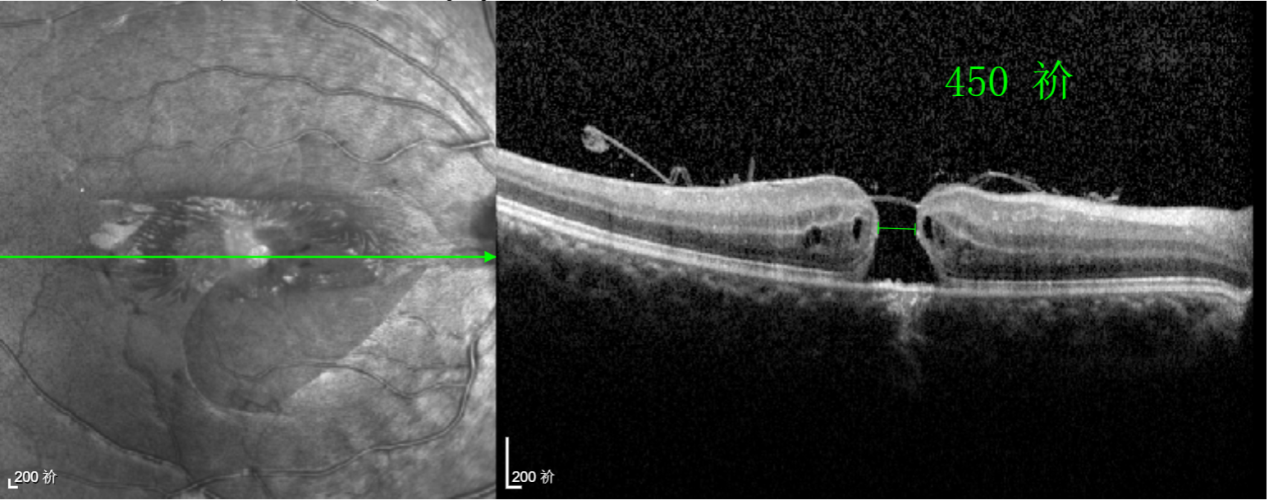

經(jīng)過詳細(xì)的檢查和評(píng)估,王曉波主任決定采用“內(nèi)界膜翻轉(zhuǎn)覆蓋聯(lián)合粘彈劑固定術(shù)”為誠誠進(jìn)行治療。

術(shù)中,醫(yī)生精細(xì)剝離黃斑區(qū)的內(nèi)界膜后,并非直接丟棄,而是巧妙地給它翻個(gè)面,讓它變成一塊天然“創(chuàng)可貼”,嚴(yán)密覆蓋在黃斑裂孔的表面。覆蓋的內(nèi)界膜像微型支架一樣撐住裂孔邊緣,防止它擴(kuò)大;同時(shí),這層膜本身含有能促進(jìn)生長的“養(yǎng)分”,能顯著刺激裂孔周圍的視網(wǎng)膜組織像爬山虎一樣快速生長、蔓延過來,最終把裂孔“補(bǔ)”好。

除此之外,利用自體組織覆蓋為黃斑裂孔提供了理想的愈合環(huán)境,裂孔閉合速度顯著快于傳統(tǒng)方法。誠誠接受手術(shù)24小時(shí)后,檢查可見內(nèi)界膜瓣位置良好;術(shù)后1個(gè)月,黃斑裂孔已經(jīng)閉合,視力恢復(fù)到0.5;術(shù)后兩個(gè)月,視力進(jìn)一步提升到0.7。